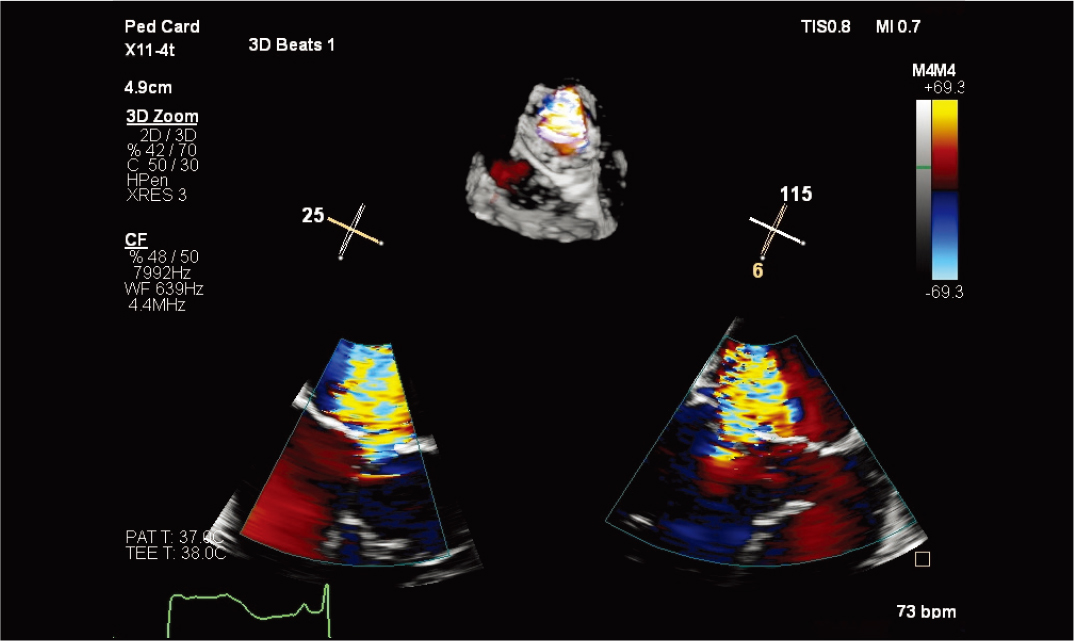

X11-4t 探头的儿科 3D 彩色 |